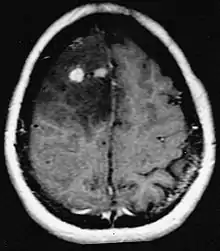

Le lymphome primitif du système nerveux central représente environ 2 pour cent à 3 pour cent de toutes les tumeurs cérébrales chez les patients ayant un système immunitaire normal. Ils surviennent plus fréquemment chez les hommes de plus de 55 ans jusqu'à 60 ans. Près de la moitié de tous les lymphomes surviennent chez des patients de plus de 60 ans et environ un quart chez des patients de plus de 70 ans. L'incidence semble augmenter avec l'âge, mais la raison n'est pas encore claire. Les patients dont le système immunitaire est affaibli sont plus à risque de développer un lymphome du SNC, de sorte que ceux qui ont subi une greffe d'organe ont une immunodéficience congénitale ou une maladie auto-immune, ou sont infectés par le virus de l'immunodéficience humaine. Les lymphomes cérébraux associés au VIH sont associés au virus d'Epstein-Barr, en particulier chez les patients dont le nombre de lymphocytes CD4 est inférieur à 500 cellules par millimètre cube dans le sang. La plupart des lymphomes du SNC sont des lymphomes diffus à grandes cellules B.

Les patients souffrent d'une variété de symptômes caractéristiques d'une lésion massive focale ou multifocale. L'IRM montre généralement des tumeurs avec un rehaussement de contraste homogène au sein de la substance blanche périventriculaire profonde. La multifocalité et le rehaussement inhomogène sont typiques des patients dont le système immunitaire est affaibli. L'analyse du lymphome du SNC est extrêmement importante dans le diagnostic différentiel de la néoplasie cérébrale. Il est à noter que l'administration de corticoïdes peut entraîner la disparition complète du rehaussement, rendant difficile le diagnostic des lésions. Par conséquent, si un lymphome du SNC doit être pris en compte dans le diagnostic différentiel, les corticoïdes doivent être évités à moins que l'effet de masse ne provoque un problème grave et immédiat chez le patient.

La biopsie de la lésion suspectée est cruciale. Contrairement au lymphome systémique à grandes cellules B, dans lequel la chimiothérapie et la radiothérapie sont efficaces et le traitement des lésions localisées est curatif, le lymphome du système nerveux central répond généralement au traitement initial mais réapparaît ensuite. Comme pour le lymphome systémique, le rôle de la chirurgie est principalement limité à l'obtention d'échantillons de tissus appropriés pour le diagnostic.

Dans le passé, la radiothérapie était administrée à l'ensemble du cerveau (panencéphalique). La médiane de survie est d'environ 12 même avec des lésions localisées Mois. La récidive affecte généralement le site de la blessure précédente ainsi que d'autres régions. Les réponses à la chimiothérapie sont plus prometteuses. Les essais cliniques dans lesquels le méthotrexate à haute dose seul a été utilisé comme premier traitement et la radiothérapie a été retardée jusqu'au moment de la rechute ou de la progression ont montré une meilleure survie globale que la radiothérapie seule. Encore plus efficace était la combinaison de méthotrexate, vincristine, procarbazine, méthotrexate intrathécal, cytarabine et radiothérapie panencéphalique et cytarabine, ou l'utilisation d'une chimiothérapie intra-artérielle avec méthotrexate intra-artériel, cyclophosphamide injecté par voie intraveineuse et étoposide après modification du sang. barrière cérébrale avec du mannitol. La médiane de survie sous méthotrexate était de 24 jusqu'à 40 mois beaucoup plus élevé qu'avec la radiothérapie seule (extrêmes 24 jusqu'à 40 mois). Dans certains cas, la radiothérapie n'est utilisée que pour les rechutes lorsqu'il y a une régression initiale avec la chimiothérapie. Des cas de survie longue ont également été rapportés sans radiothérapie.